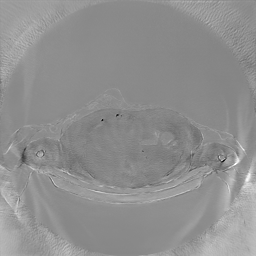

III-C Uncertainty analysis

Classical diffusion models reconstruct images by progressively denoising from an initial Gaussian noise image, a process that inherently introduces uncertainty due to random noise initialization. In contrast, I2SB directly learns a diffusion bridge between two sample distributions, effectively bypassing the need for random noise sampling and thereby reducing reconstruction variability.

To assess the uncertainty of our method, we performed multiple reconstructions using different random seeds. As shown in Fig. 3, the ground truth and representative sampled images are presented in Fig. 3(a) and (b–d), respectively. The mean reconstruction and pixel-wise standard deviation across runs are displayed in Fig. 3(e) and (f). Only minimal differences are observed between reconstructions, indicating that I2SB produces highly consistent results. These findings confirm that, compared with classical diffusion models, I2SB substantially reduces uncertainty across repeated reconstructions.